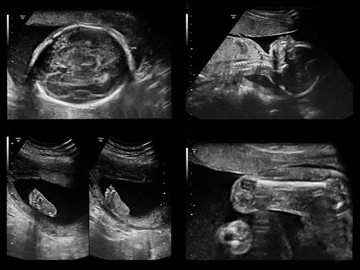

При нормальном течении беременности в третьем триместре проводится абдоминальное ультразвуковое исследование. Экспертный УЗИ аппарат Resona 6 в клинике «АБИА» позволяет получить трехмерное изображение малыша, что повышает точность диагностики. Готовиться к завершающему скринингу не нужно, важней всего хорошее настроение и отсутствие волнения у мамы.

Пройти скрининг УЗИ в третьем триместре беременности предлагает клиника «АБИА». Наши специалисты максимально внимательно отнесутся к здоровью как малыша, так и будущей мамы. Оборудование высокой точности, чуткость персонала и профессионализм врачей - причины обратиться именно к нам. У нас вы можете получить фото плода и запись УЗИ на usb, в том числе в трехмерном изображении.